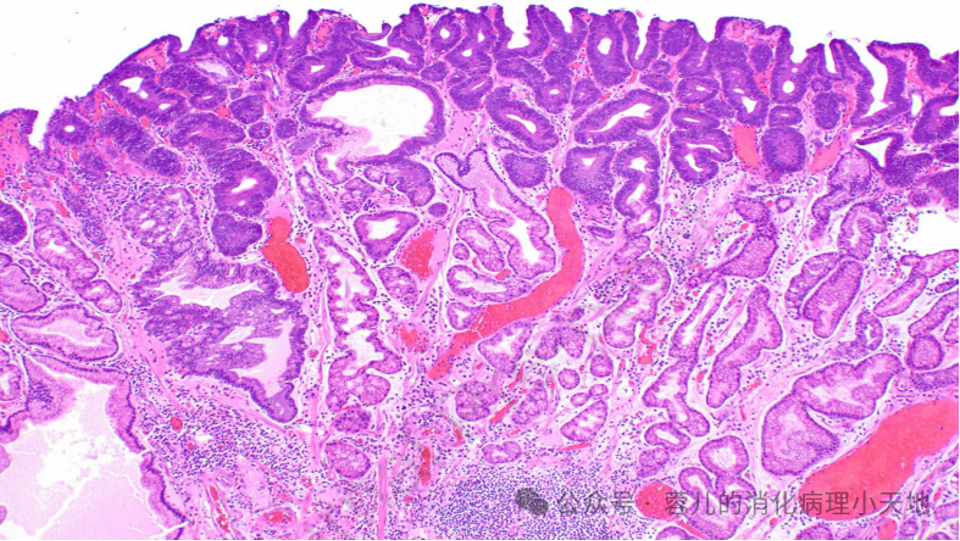

形成病变的胃异型增生(肠型腺瘤)具有肠型表型,表现为密集的腺体,由深染的肿瘤细胞排列而成,累及胃窦黏膜

病变细胞缺乏粘蛋白,并含有铅笔状假复层核,这些核保持与基底膜的关系

组织学特征:密集排列的腺体,由深染的肿瘤细胞构成,细胞缺乏粘蛋白,含铅笔状假复层核,且核与基底膜保持关系